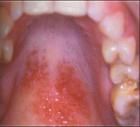

粘膜病在我们的日常生活中,存在的几率是比较频繁的,它包括的范围也是比较广泛的,几乎所有的人都存在有粘膜病的侵袭,只是发生的程度有所不同,下面就请北京京城皮肤医院,就粘膜病的一些发生特点为我们做详细的服务。

一、口腔黏膜的发生,是随着年龄的增长而逐渐发生的,主要是因为患者口腔的*力表现出下降的状态,而在生理上也存在有一定的缺陷,对于成年人来说,由于成长激素的分泌逐渐减少,口腔对于维生素的吸收能力反而不及儿童的生长期;

二、对于具有复发性的口腔溃疡症状来说,属于多*的遗传病,如果父母表现比较严重的话,子女在遗传上的可能性就会比较的大。尤其上了年纪的老人家,身体容易出现胃肠功能的紊乱现象,体内缺乏铁、锌等微量元素,睡眠不好也会导致精神出现紧张,劳累或感冒时,都会诱发口腔溃疡的症状。

对于粘膜病的发生来说,它的症状表现是比较轻微的,,因此比较容易被患者所忽略,当病症表现比较严重时,才进行治疗,难度也就相对会变得大一些。因此在日常的生活中,一定要及时进行治疗。如果您对上述的病情还有不清楚的地方,请来电预约010-64888999,或直接登录我们的网站,跟专家做面对面的交流http://www.pf110.com/将为您提供较满意的答复.